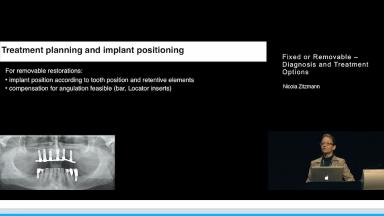

Restoring the edentulous maxilla with a fixed dental prosthesis or a removable overdenture is a complex and challenging procedure. The crucial factors are discussed involved in deciding whether a fixed or removable prosthesis should be planned in fulfilling the patient’s preference for optimal esthetics, phonetics, comfort and function.

A treatment planning concept is presented which enables the practitioner to check the decisive parameters during the first examination and to take the final decision with the help of the reformatted CT-scan.

Implant placement in accordance with the selected prosthetic solution and avoidance of any compromised solutions can be attained when following this treatment plan which has been tested clinically.